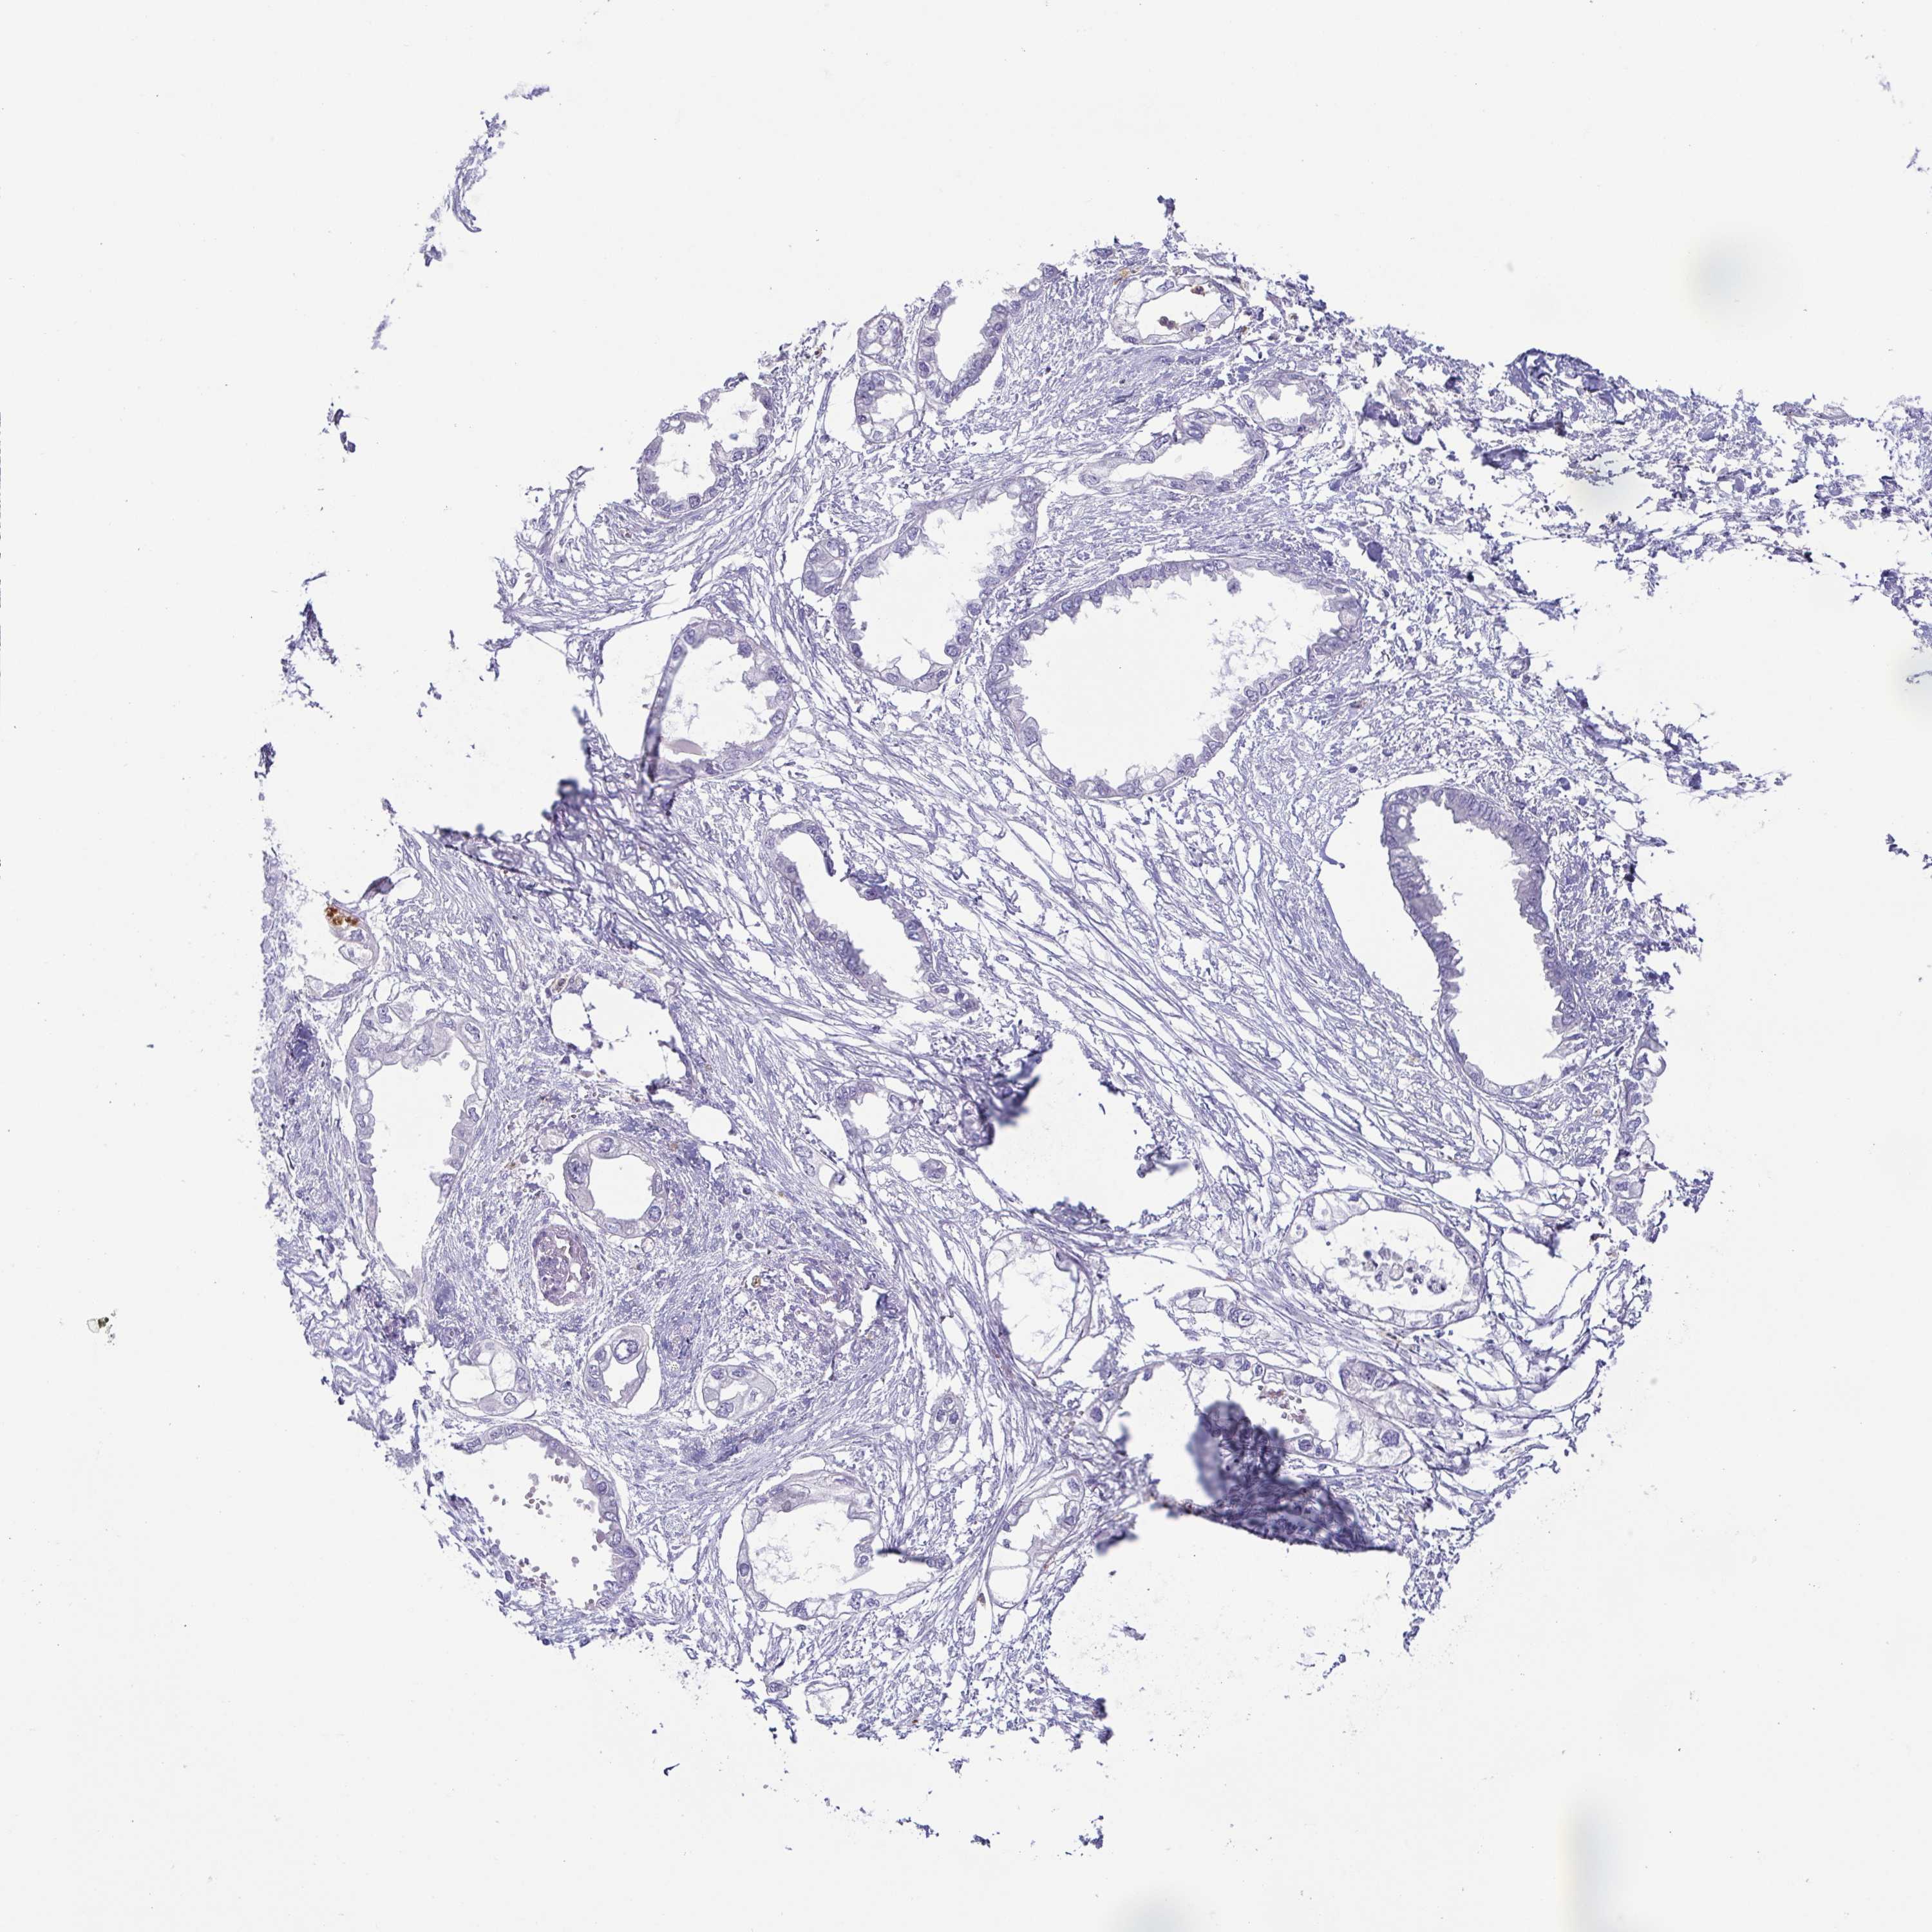

ENDOMETRIAL CANCER - Protein expressioni

A mouse-over function shows sample information and annotation data. Click on an image to view it in a full screen mode. Samples can be filtered based on level of antibody staining by selecting one or several of the following categories: high, medium, low and not detected. The assay and annotation is described here.

Note that samples used for immunohistochemistry by the Human Protein Atlas do not correspond to samples in the TCGA dataset.

Antibody stainingi

Antibody staining in the annotated cell types in the current human tissue is reported as not detected, low, medium, or high, based on conventional immunohistochemistry profiling in selected tissues. This score is based on the combination of the staining intensity and fraction of stained cells.

Each image is clickable and will lead to virtual microscopy that enables deeper exploration of all samples and also displays staining intensity scores, fraction scores and subcellular localization as well as patient and tissue information for each sample.

Antibody HPA055851

Antibody HPA075964